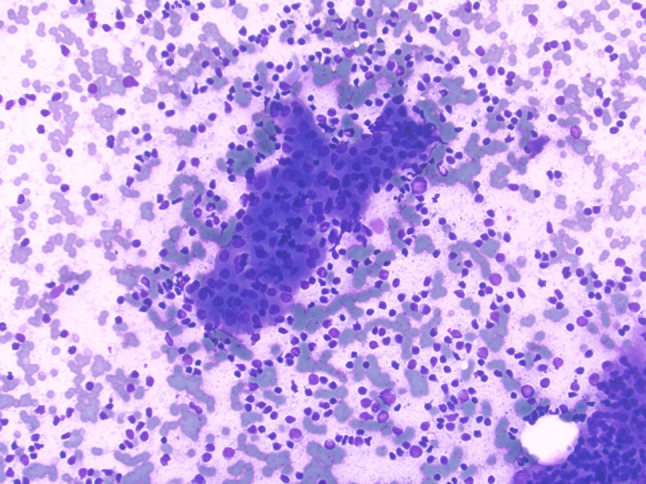

Fig. 7.

FNA smear procured from a Warthin tumor showing a sheet of oncocytic epithelial cells associated with background polymorphous lymphocytes (Diff Quick stain, magnification × 20)